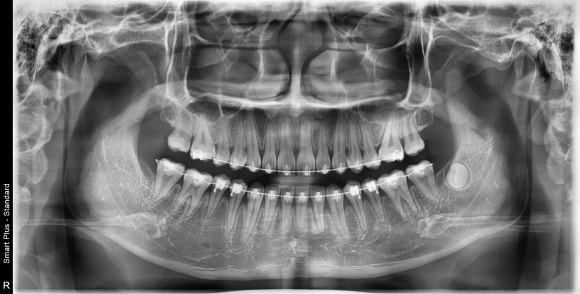

X-ray 촬영,

3D 구강 스캔,

측모 두부 계측 분석 등을 통해 발치가 필요한지를 판단하게 됩니다.